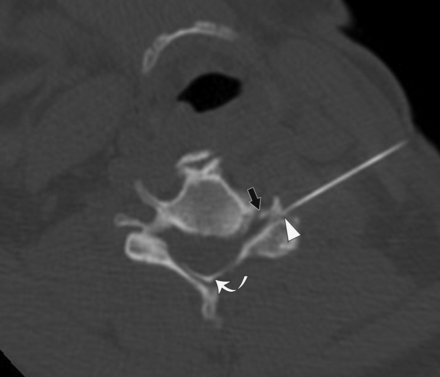

A 51-year-old woman with left-neck pain radiating to the forearm who had a CT-guided CTSI of the left C5 nerve root. The needle angle is 28°, and the tip of the needle is in the junctional location (arrowhead). Contrast is seen in the extraforaminal and intraforaminal (black arrow) regions. Contrast is also present in the central epidural space (curved arrow).